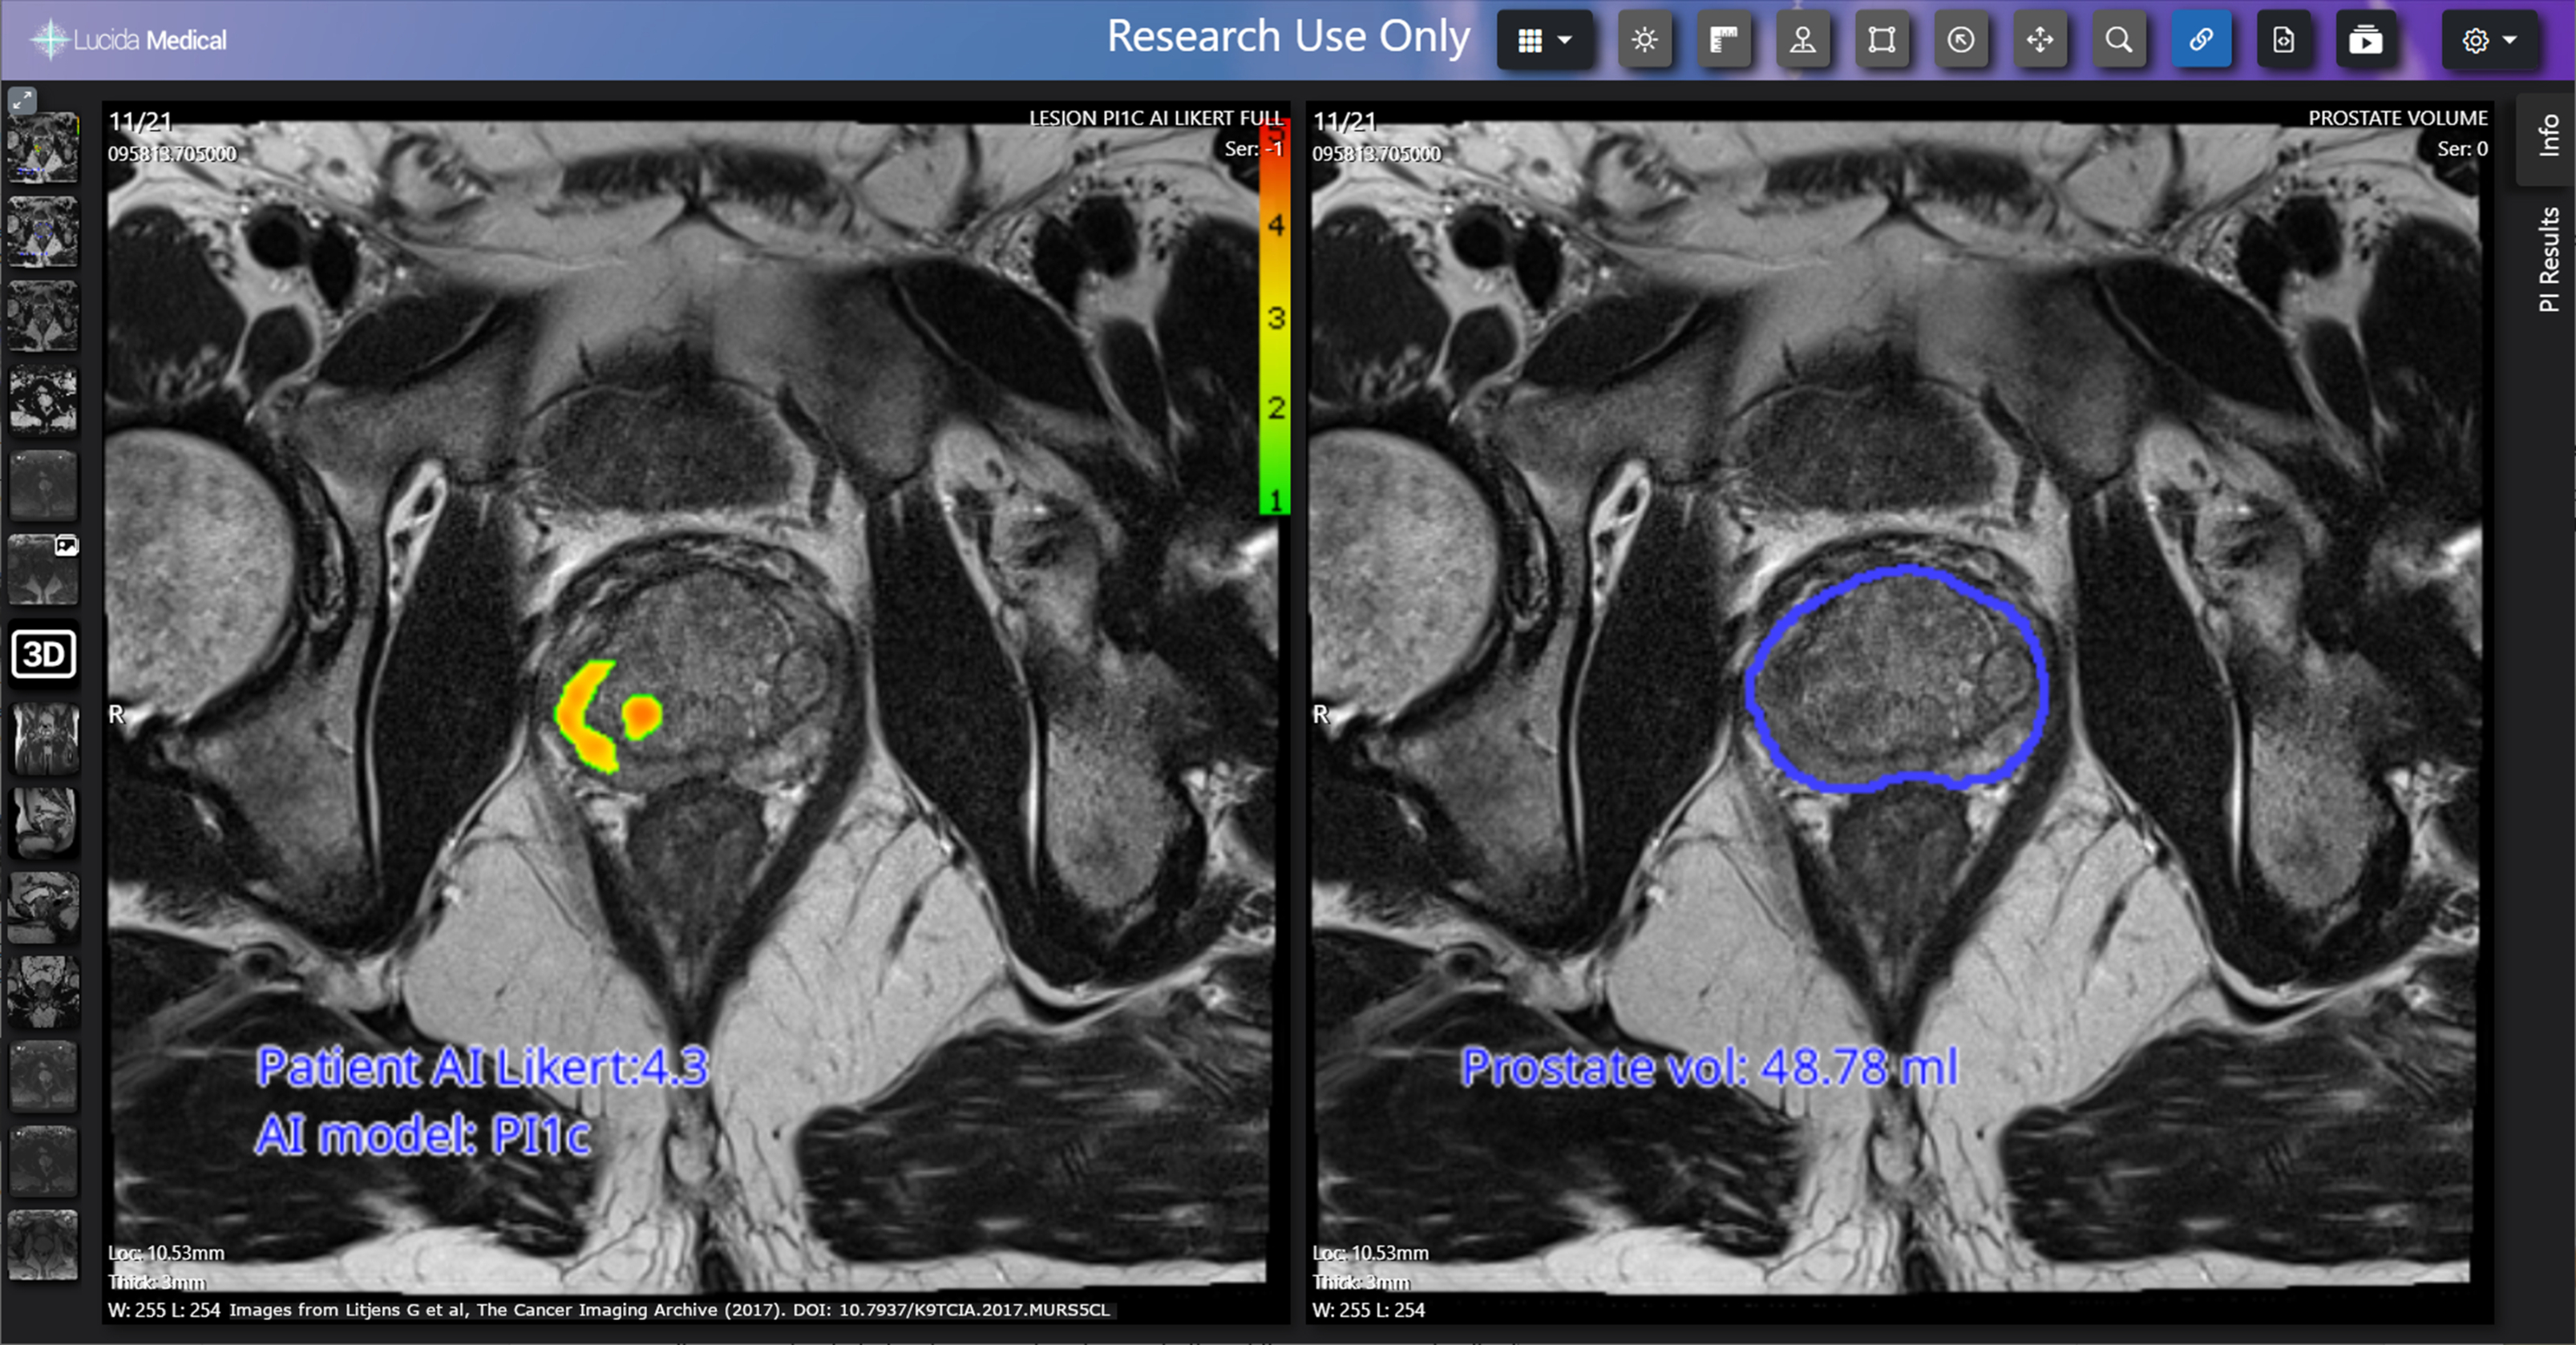

Industry collaboration has been instrumental in leveraging artificial intelligence to enhance radiological operations and patient care. A deal with Lucida Medical is being explored as part of a Topol Fellowship feasibility project to assess the role of AI in triaging prostate cancer patients, and they've received funding to evaluate radiology AI products from Aidoc, Qure.AI, and Radiobiotics. Also, industry-academic collaborations with Mirada Medical and Oxford Heartbeat have been secured from Innovate UK.